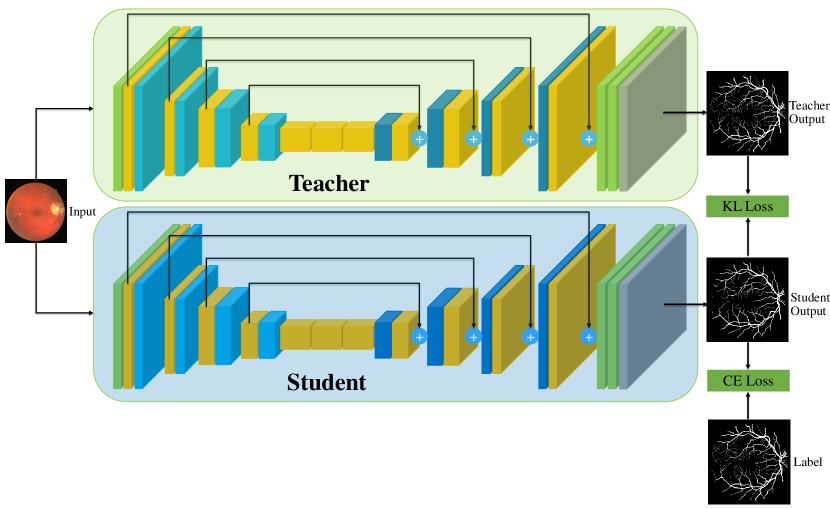

VI-A Retinal Artery and Vein Segmentation

As reported in Table IV, we compared the SegRAVIR model against competing deep learning-based segmentation approaches on the RAVIR dataset. Evidently, SegRAVIR outperforms these methods as judged by all metrics for artery and vein classes with a healthy margin. In terms of Dice score, SegRAVIR outperforms CE-NET, IterNet and AG-Net by , and for artery segmentation and by , and for vein segmentation, respectively. Fig. 4 presents a qualitative comparison of the semantic segmentation outputs of SegRAVIR, CE-Net, and U-Net. Specifically, SegRAVIR yields more accurate vessel topology (i.e., thickness and orientation) segmentation with higher pixel-wise classification accuracy.

Table V presents quantitative performance benchmarks of SegRAVIR and other competing approaches for retinal artery and vein classification on the RITE dataset [11]. SegRAVIR outperforms previous state-of-the-art approaches in terms of accuracy, sensitivity, and specificity. Fig. 5 provides a qualitative comparison between segmentation outputs of SegRAVIR and the method of Hemelings et al. [40] on the RITE test set.